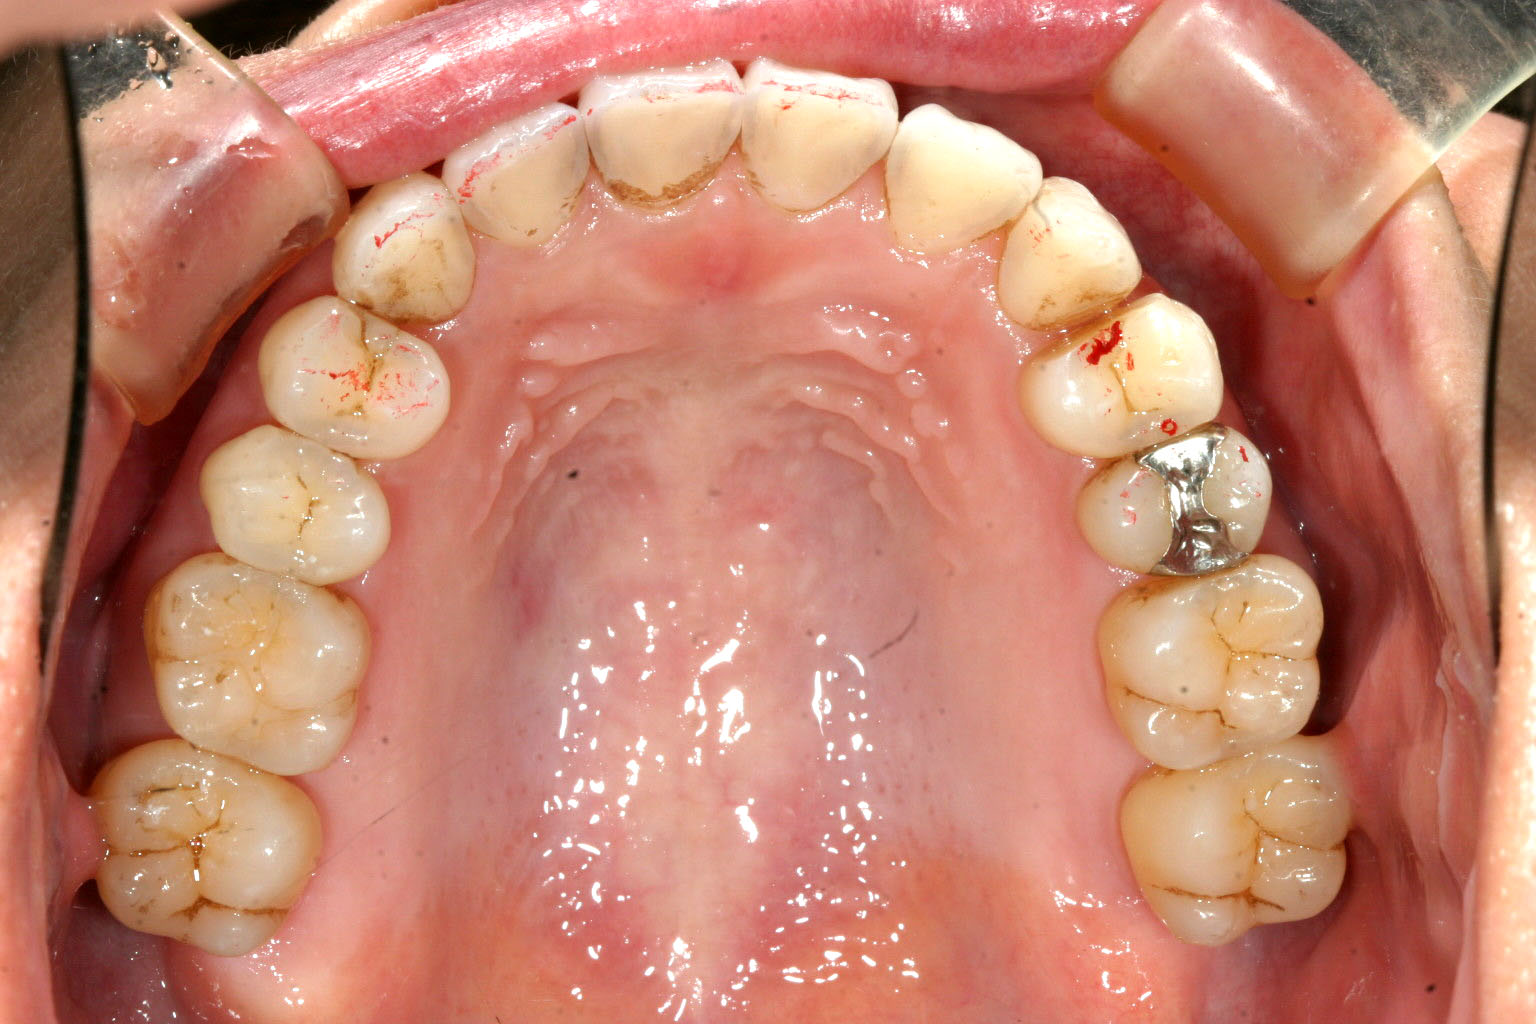

今回の症例も良く有るケースなんですがアーチが狭く前歯に叢生が出ているケースです。

この様な場合アーチの拡大とIPR(歯と歯の隙間を削る)を行う事により出っ歯になる事なく

凹んだ歯を前に出しています。